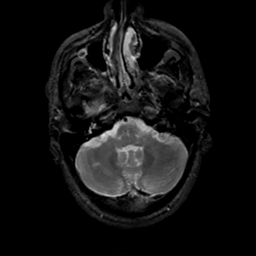

MR Study #17, July 7, 1991 -- Slice #10